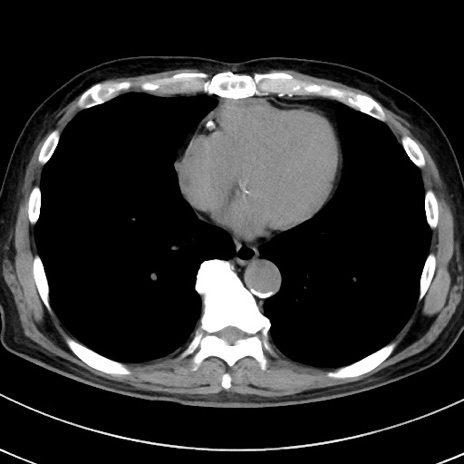

症例38(横断像)

【症例】70歳代 男性

【主訴】腹痛・嘔吐

【現病歴】昨晩より、嘔吐・腹痛あり。今朝になっても嘔吐あり。来院。

【既往歴】心臓バイパス手術、開腹胆摘、腸閉塞

【身体所見】BP 107/71mmHg、HR 116/min、腹部:平坦、軟、下腹部に軽度圧痛あり。反跳痛なし。

【データ】WBC 15100、CRP 0.32